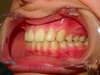

Intrabuccale droite - Avant traitement 1 (25-01-2021) - 4

Intrabuccale droite - Fin de traitement (24-09-2023) - 32